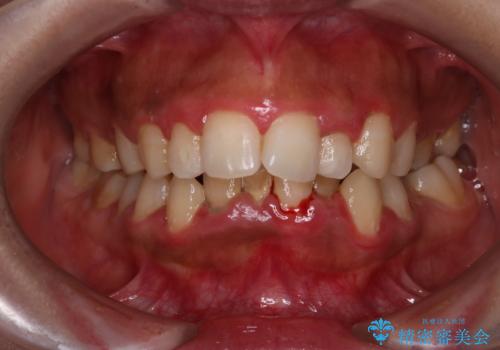

前歯と奥歯のガタガタを矯正で改善

- 患者様は、前歯と奥歯のガタガタ(叢生)を改善し、正面から見た時の歯並びを美しく整えたいとのご要望で来院されました。診断の結果、非抜歯での矯正が可能と判断し、インビザラインを使用する治療計画を立案しました。透明な矯正装置で目立ちにくい治療を行いながら、前歯と奥歯の両方を整列させることを目標にしました。

インビザラインを用いて、前歯の見た目を重視しつつ、奥歯のガタガタも改善しました。特に正面から見た際の美しい歯列を意識し、段階的に歯を移動させることで、全体の調和を図りました。治療中は、適切な装着時間を守ることや、装置の清潔を保つことが重要でした。また、歯肉や歯列全体に無理な負担がかからないように移動を管理しながら治療を進めました。結果として、前歯と奥歯がきれいに並び、見た目にも機能的にも満足いただける仕上がりとなりました。